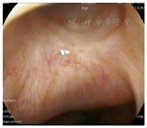

出院后继续给予鼻腔冲洗及外用糠酸莫米松等鼻喷药物治疗,清除术后结痂,减轻局部黏膜水肿对症处理。术后2个月复诊见鼻底开窗处黏膜上皮已形成(图10),继续随访中。